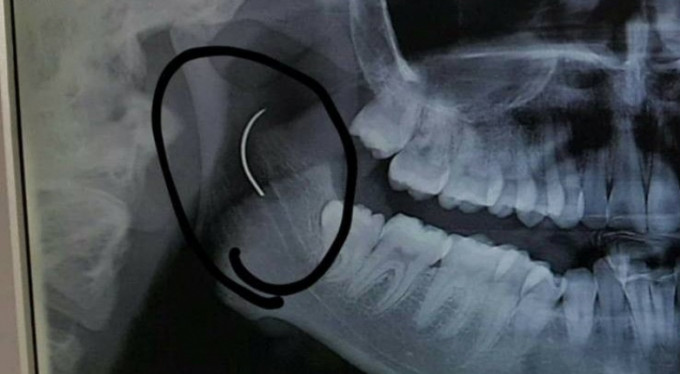

Soma Devlet Hastanesi'nde bademcik şikayetiyle 1999 yılında ameliyat olan Meltem Cansız'ın boğazında iğne unutuldu. 18 yıl boyunca boğazında iğne ile yaşayan ve şu anda 21 yaşında olan Meltem Cansız'ın tüm hayatı acı ve ağrılarla geçti. Boğazındaki iğnenin acıları günden güne yıldan yıla artan Meltem Cansız, 11 yıl sonra 14 yaşında iğnenin fark edilmesiyle Ege Üniversitesi'nde bıçak altına yattı ancak ameliyatı başarısız geçti. Lise öğreniminden sonra sağlık sorunları nedeniyle üniversiteye hazırlanamayan Meltem Cansız, acılarına rağmen yılmadı sabırla bekledi ve geçirdiği başarılı ameliyatla o iğneden 18 yıl sonra kurtuldu.

Boğazındaki iğneyle geçen 18 yılını anlatan Meltem Cansız, "3 yaşında geçirdiğim bademcik ameliyatında iğne boğazımda unutulmuş. Daha sonra iğneden dolayı 11 yıl sonra 14 yaşındayken kulak rahatsızlığım ortaya çıktı. Kafamın sağ tarafı ağrımaya başladı. Doktora gittik, hiçbir şey olmadığını söylediler. Sonrasında beni MR çekilmek üzere Akhisar'a yönlendirdi. Gecenin bir vakti MR'a girdim. Ancak bir türlü çekemediler. Benim üzerimde toka vs. metal bir şey olduğunu söylediler baktılar ancak bir şey yoktu. Üç yada dört defa MR'a girdim. Ancak bir türlü çekemediler. Sonra doktorumuz röntgene yönlendirdi. Röntgen görüntüsünde ameliyattan kalma bir çengelli iğnenin boğazımda olduğu görüldü. Bunun için beni Ege Üniversitesi'ne sevk ettiler. Burada doktorlar bu ameliyatı yapabileceklerini ancak riskinin çok olduğunu söylediler. Biz yine de kabul ettik. 1,5 saatlik operasyon geçirdim ancak iğneyi bulmadıklarını söylediler. 2 sene kadar araştırma yaptık. Birçok hastaneyle görüştük. Ancak ayağımda bir rahatsızlık meydana geldi. Ayağım için Ege Üniversitesi'ne gittik. Tekrardan beni ameliyat eden doktorumla görüştüm. 'Seni ben ameliyat ettim, tekrardan buna kalkışamam' dedi. MR'a da giremezsin dediler. 'Sen bununla yaşamayı öğren' en azından bunun için çabalama alınmaması daha iyi dediler. Ben daha genç bir kızım sonuçla bu iğneyle ömür boyu yaşayamazdım. Yaşanan bu olumsuzların ardından araştırmalarımız neticesinde en son İzmir'de özel bir hastaneye gittik. Oradaki doktorum Çağlar Çallı bey bana umut verdi. 'Bu iğneyi alacağız' dedi. İnancımı kaybetmedim, sonucun ne olacağını bilmeden girdim ben o ameliyata. Ölüm, felç olma riskim çok fazlaydı. 'Yaşayamayabilirsin' dediler, biz bile bile lades dedik. Sonucu da güzel oldu" dedi.

Ege Üniversitesi'ne gittiklerini belirten baba Cansız, iğnenin şah damarına çok yakın olduğunun söylendiğini belirterek şunları söyledi: "Doktorlar çok tehlikeli bir ameliyat olacağını yanlış ya da en ufak bir hatada kızımızın bir tarafının felç kalabileceğini veya hayatını kaybedebileceğini söylediler. Biz bu riski göze alarak ameliyata müsaade ettik. Fakat iğneyi görüldüğü yerde bulamadıklarını söyleyerek alamadılar. Sonra İzmir Çiğli'de özel bir hastanede denedik. Kendisine binlerce kez teşekkür. Allah razı olsun. Çocuğumun boğazındaki iğneyi aldı. Dünyalar bizim oldu."